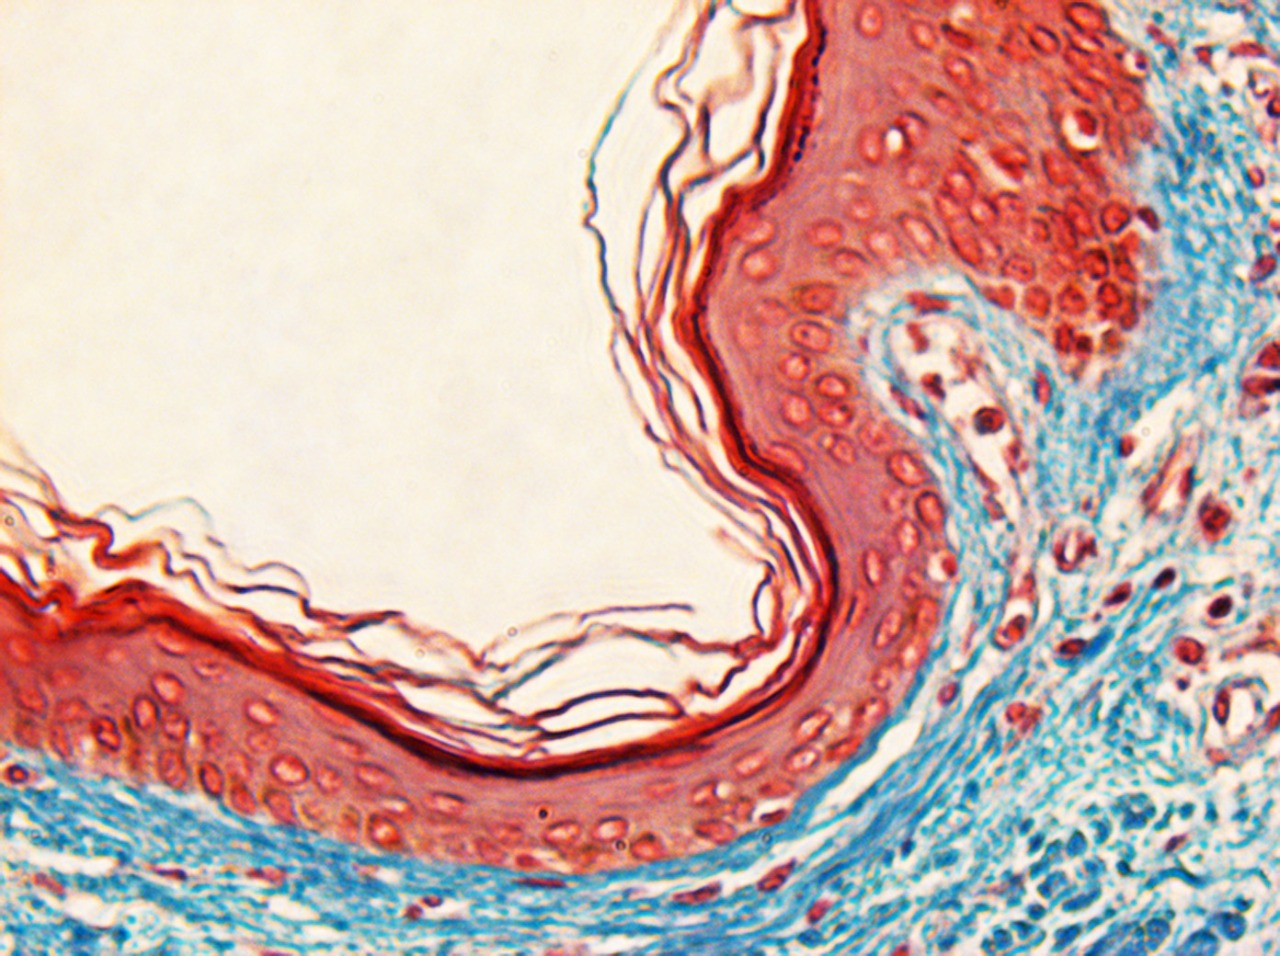

Pele